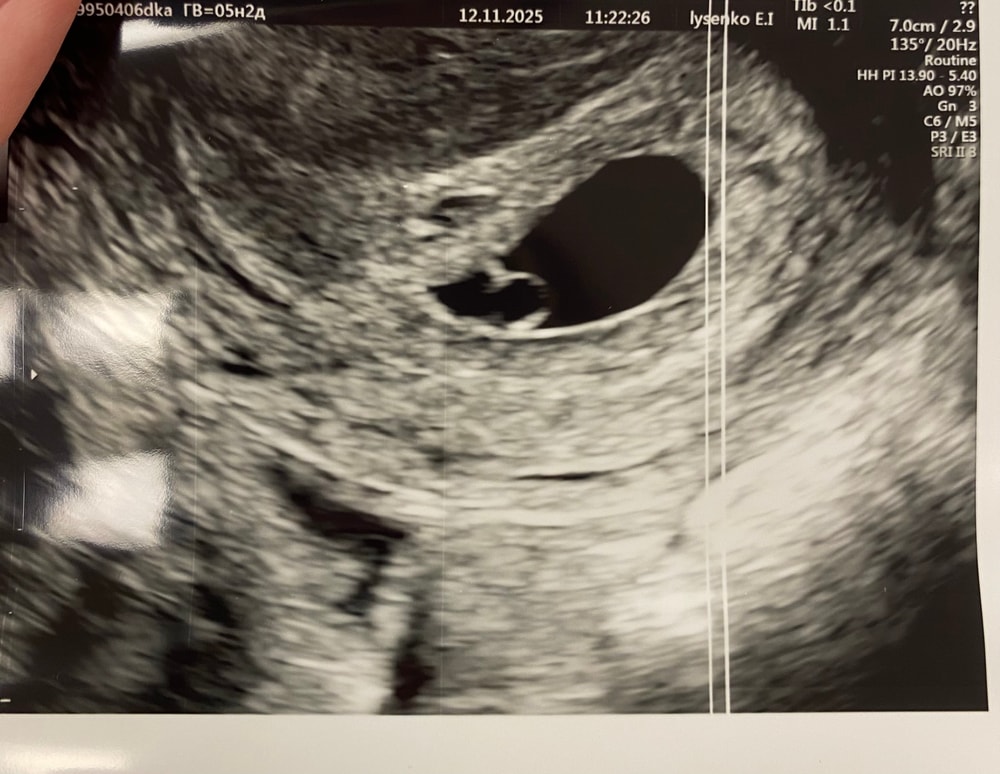

Утром побежала на узи..И о боже🙏😭Мое бриллиантовое колечко,как же я тебя ждала😭Пульсирует сердечко❤️ И все таки один эмбриончик,второй замер😔Никаких отслоек и гематом слава богу нет.

Вот и пришло время,когда я уже могу на бб поставить кружочек🤭💕 Беременность 5нед2дня🤞